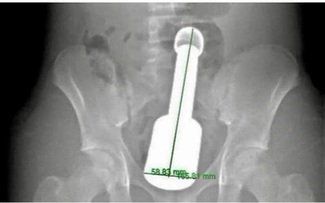

Quý ông rước họa khi đi 'độ súng': Bác sĩ cảnh báo biến chứng